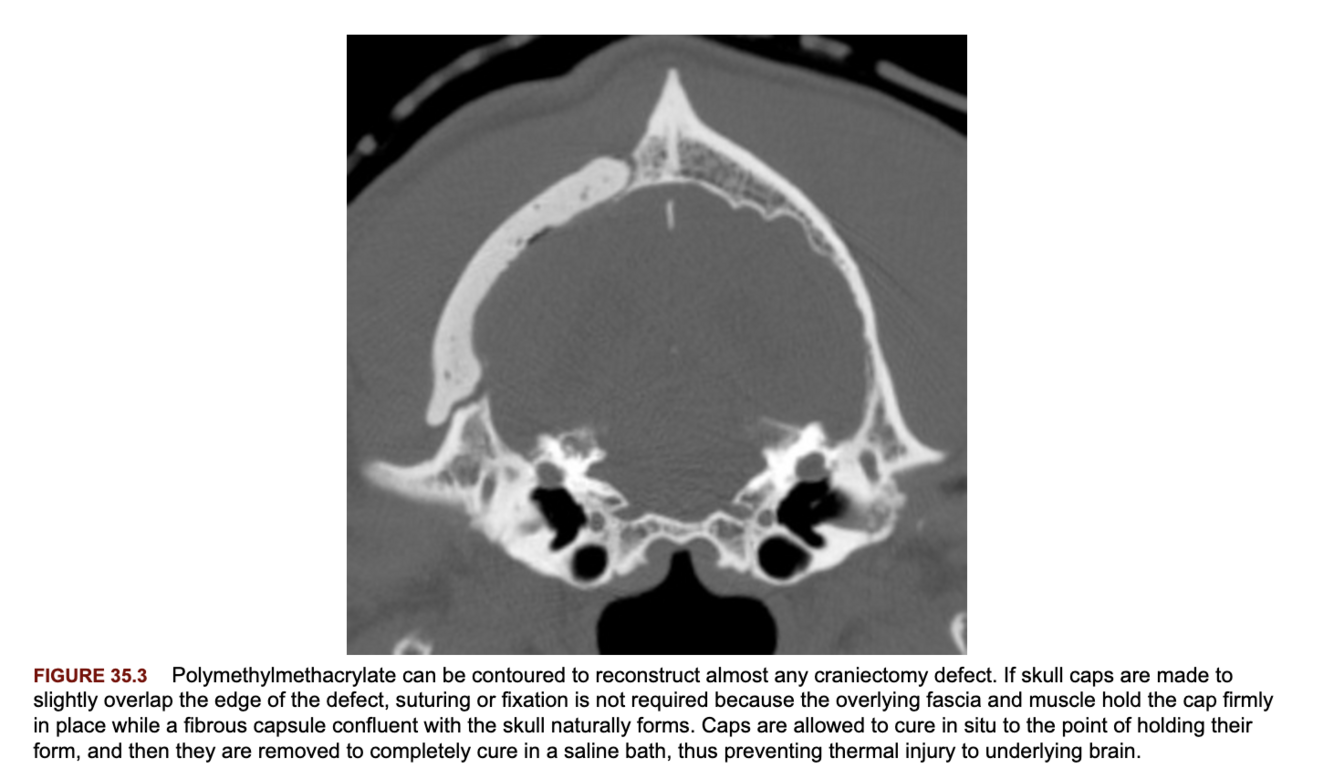

What are some options for reconstruction of the skull following craniectomy?

A

1. Replacement of the excised skull bone or calvarial allografts.

2. Acrylic cranioplasty (PMMA most common). Most common complication is infection. Should not be used in approaches which result in exposure to contaminated air from the paranasal sinuses (such as the transfrontal approach).

3. Metallic mesh. Titanium preferred due to its relative radiolucency, MRI compatability, low density, and corrosion resistance.